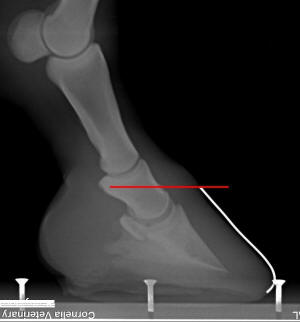

trimming more parallel to them. In figure 11, if you lowered the

heels in a straight plane from toe to heel (red line), it would

cause you to excessively thin the already too-thin sole at the

toe.Trimming or shoeing on this plane would also perpetuate the

rotated hoof capsule.

Figure 11

To accomplish this is in the field, hold the rasp “tipped up away from the toe” more parallel to the ground plane of the collateral grooves, rasping the corner of the heel. For example, the Figure 11 drawing would likely have a starting collateral groove depth of 1/8” (3mm) at the apex of the frog and 1-3/4” (43mm) at the deepest point beside the bars.

If, instead, you

chose to trim to the blue line, you would float the rasp above

the toe so that the collateral groove at the apex of the frog is

about 1” (25mm) away from the rasp as you trim the heels down to

perhaps a 1-1/4” (30mm) collateral groove height at the deepest

point beside the bars (or stop the trimming before you would

start to thin the sole that is already the correct thickness,

usually at the widest point of the foot). The bars would then

need to be tapered so that they had at least 1/4" of concavity